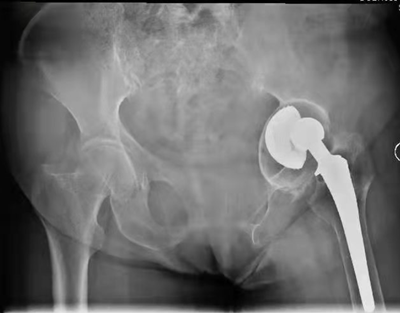

患者术前X光片。右髋置换术后,现假体松动、严重髋臼侧骨缺损

患者术后X光片。补块和假体位置满意,精准实现了术前规划

术中,导航系统追踪髋臼磨锉、假体位置和前倾角/外展角等关键角度信息,对补块位置进行示踪,将补块和假体安放的位置和角度精确到1mm和1°,最大程度避免了人工操作的误差和对重要生理结构的副损伤,大大提高了骨缺损修复的精准性和手术操作的安全性。术后,影像学显示补块及假体位置满意。